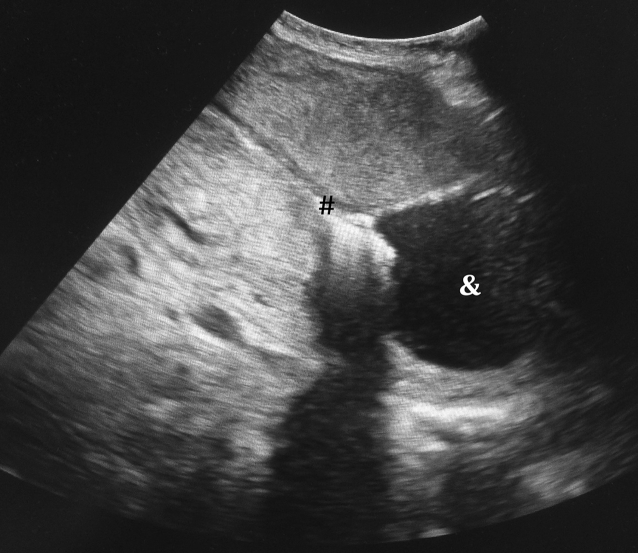

Figure 3 Vakuuminduzierte Tamponade Bei Postpartaler Blutung Springerlink